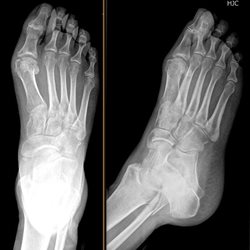

Various foot cases